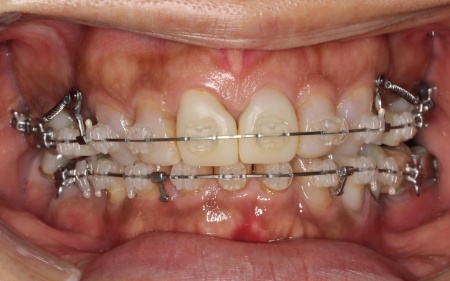

まずは、口腔内全体の矯正治療から開始します。

上顎は左上の歯が欠損していたため、左右のバランスを整える目的で、右上の歯(第1小臼歯)を抜きました。

その後、ワイヤー矯正とクローズドコイル(バネの装置)を使ったスピード矯正を行い、前歯を後方に移動させます。

下顎は残根も利用しながら、矯正用の小さなネジ「テンポラリーインプラント(インプラントアンカー)」を顎の骨に埋め込んで固定源とする方法も併用し、歯を移動させました。

矯正期間中は定期的に装置の調整を行い、歯の動きや噛み合わせの変化を確認しながら治療を進めています。